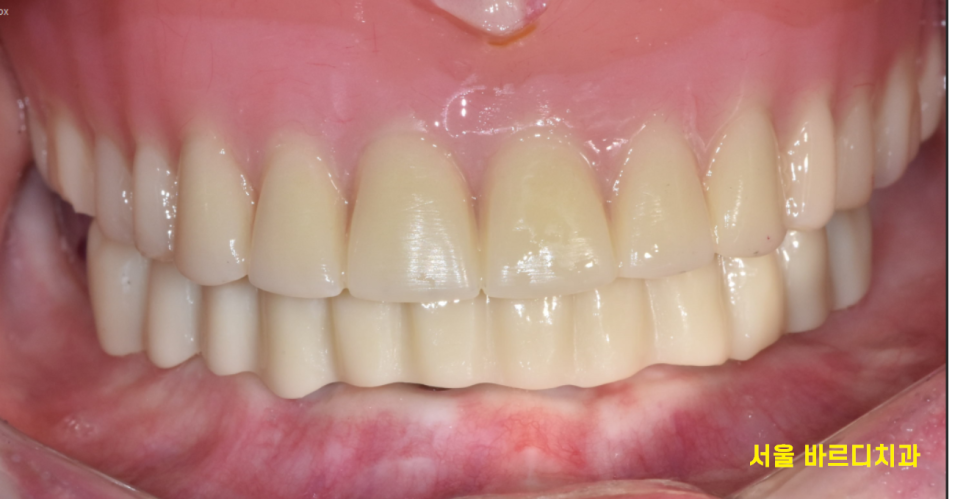

24.02.03

기둥과 보철을 연결하는 디자인을 만들면

이런 모습인데요

실제 구강 모습을 확인해 보겠습니다.

감쪽같죠~?